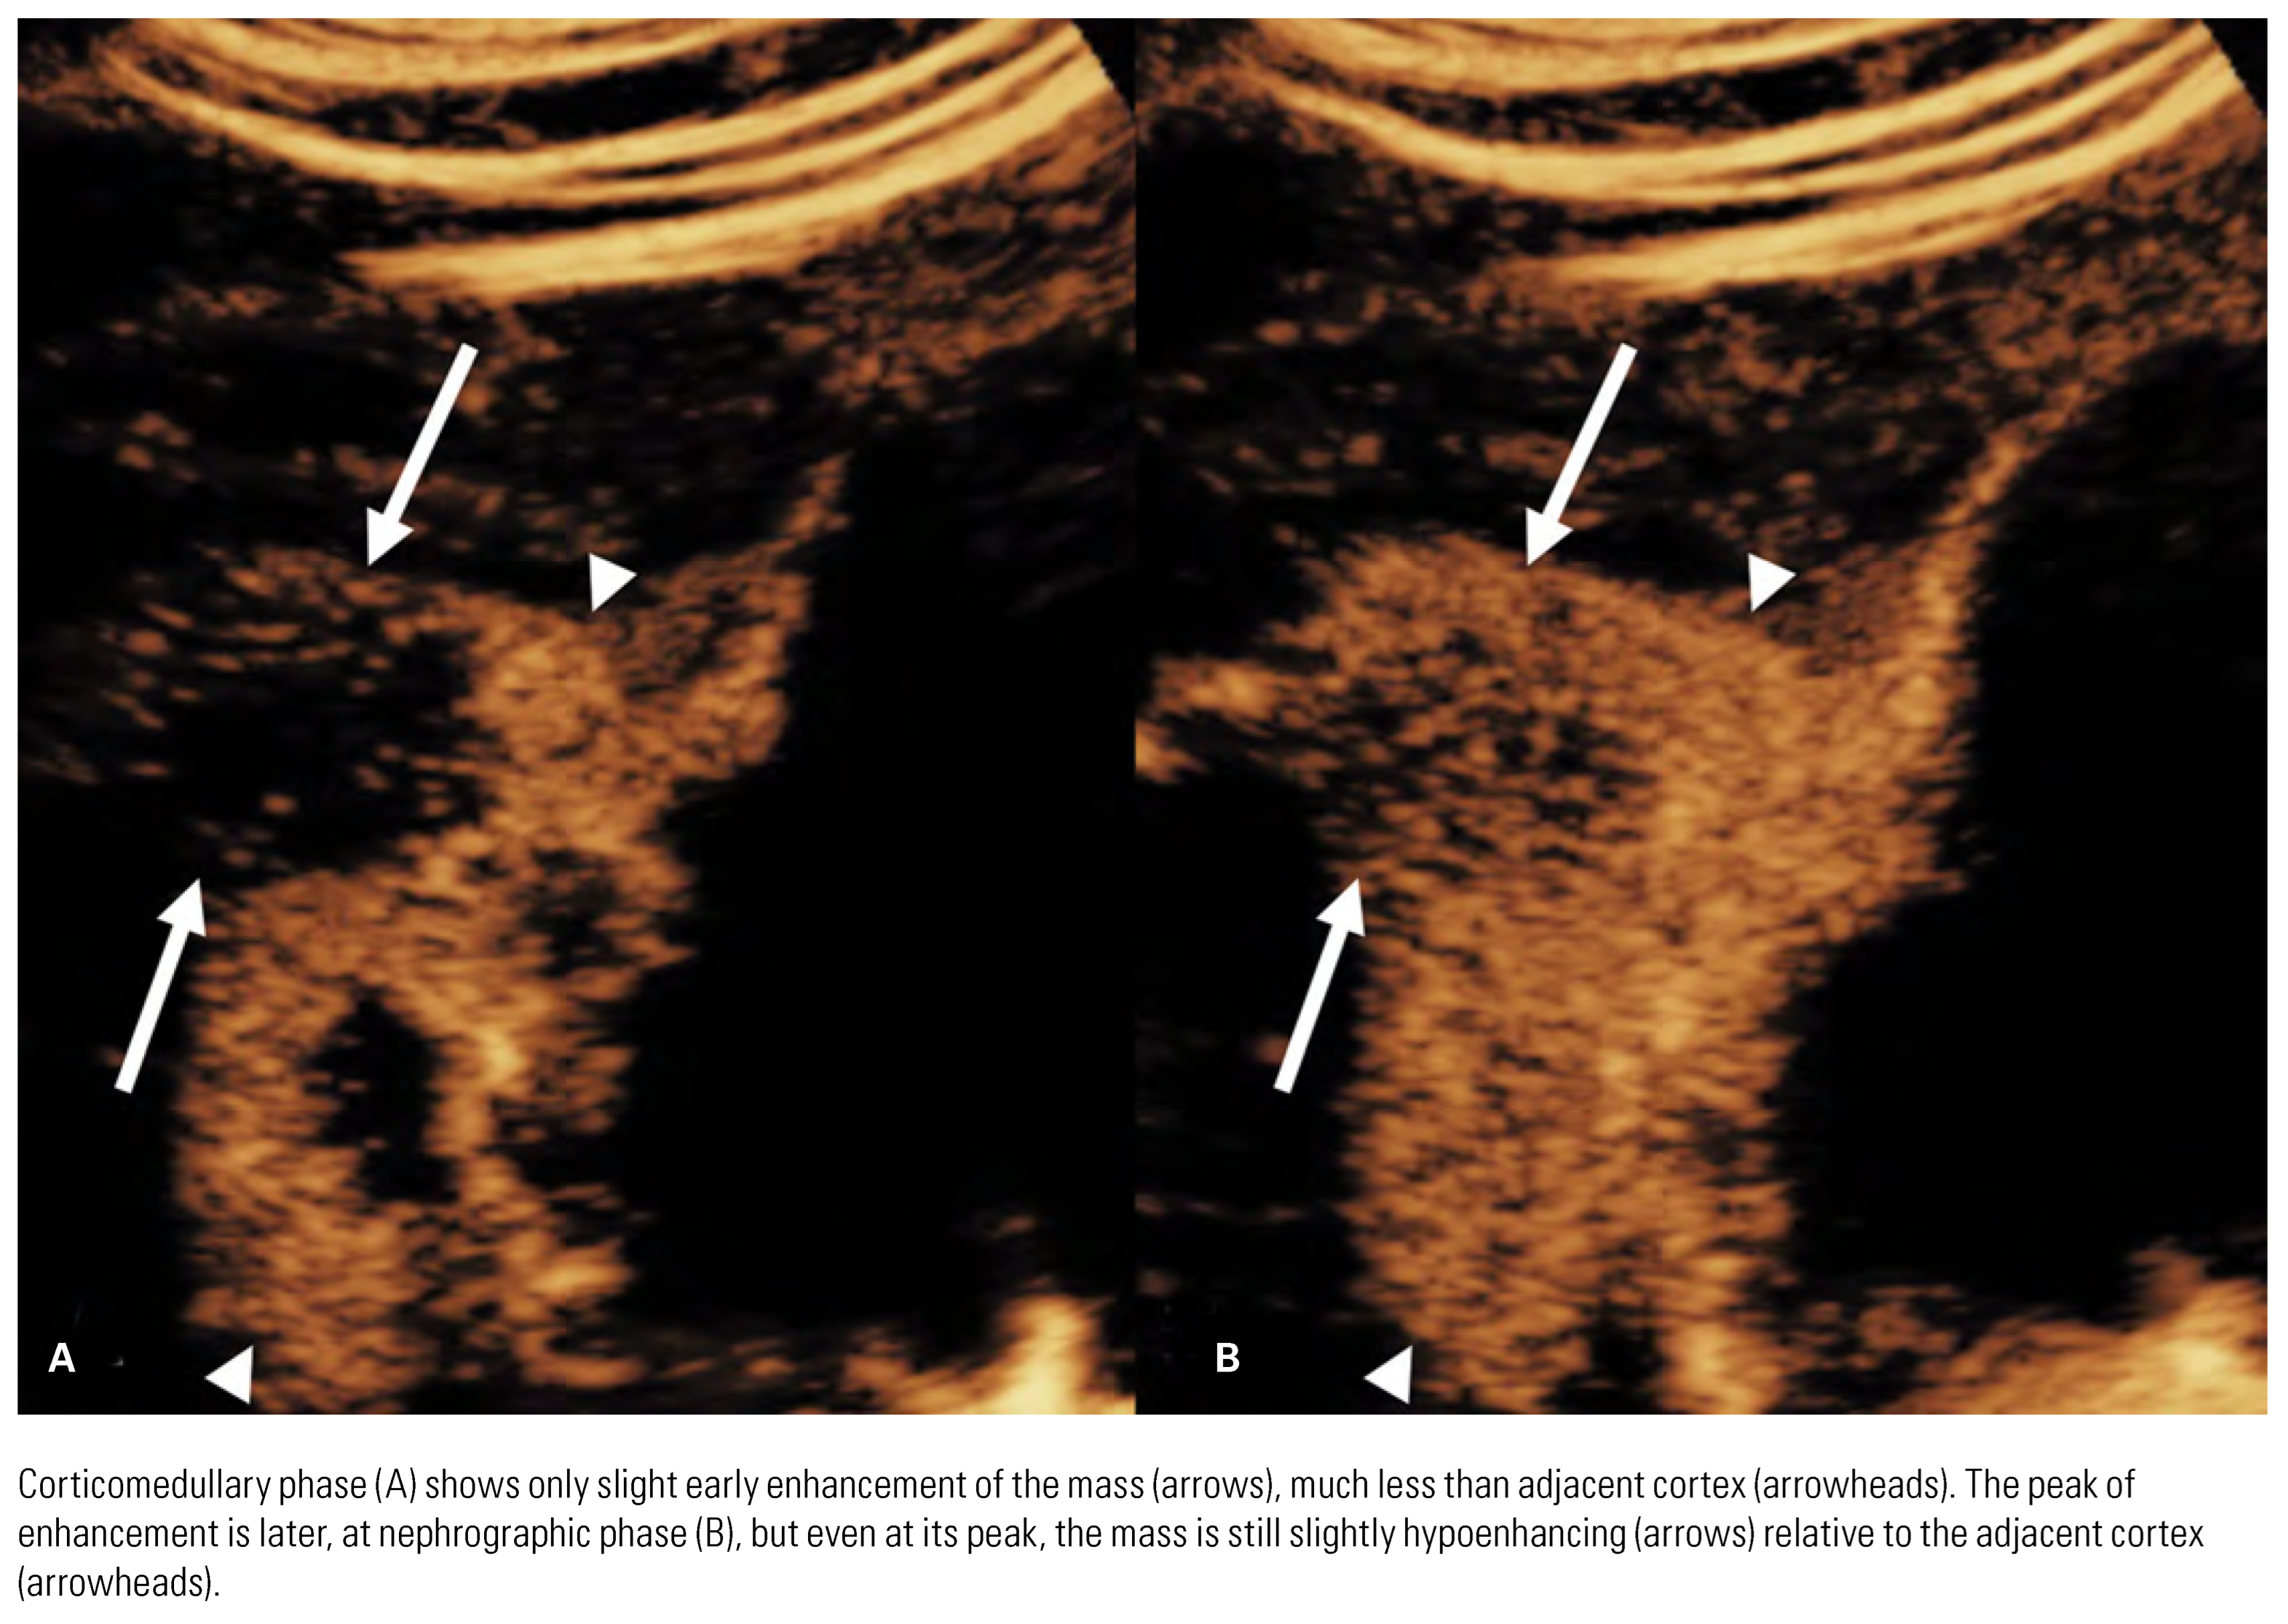

Detection and Diagnosis

Papillary Renal Cell Carcinoma

Chromophobe Renal Cell Carcinoma